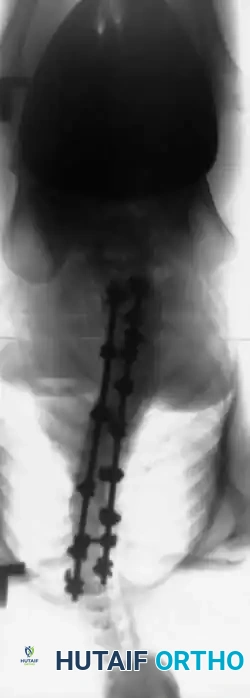

3. Instrumentation Strategies

Due to poor bone stock, multiple points of fixation are required to distribute corrective forces.

* Segmental Instrumentation: The gold standard involves rigid rod constructs (e.g., Cotrel-Dubousset principles) utilizing pedicle screws, hooks, and sublaminar wires or cables.

* Sublaminar Wires/Cables: Techniques pioneered by Luque remain highly relevant in neuromuscular scoliosis. Sublaminar cables provide excellent pull-out strength in osteopenic bone and distribute translational forces evenly across the apex of the deformity.

Associated Surgical & Radiographic Imaging

Hutaifortho's Orthopaedic Diagram